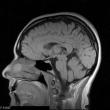

Welcome to NeuroLife.

We are here to provide you with an in-depth view into the culture, atmosphere, and writing techniques used within the broad field of Neuroscience. Use the navigation menu above to browse the various sections.